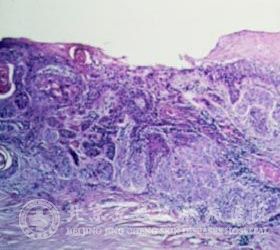

角膜鳞状*癌啊的症状哪些呢?北京京城皮肤医院指出:角膜鳞状*癌一般发生于老年人,并且以男性居多,是癌*侵犯睑裂部角膜缘部位而发生的病变。

角膜鳞状*癌较开始的时候表现为灰白色结节,然后逐渐向角膜内发展,可形成翼肉样或乳头状的肿物,有的时侯肿瘤可呈胶样隆起,基底宽,富于血管,长大后见肿物表面呈凹凸不平的菜花状,并且伴有溃疡,肿物周围血管明显扩张。角膜鳞状*癌的恶性程度低,淋巴结一般不会转移,癌肿可长时间内局限在上皮层与基质浅层,只有少数的病例在数月或数年后发生远处转移而死亡。

角膜鳞状*癌的蔓延方式有向外生长、沿角膜、结膜表面蔓延,还有一种蔓延方式就是沿角膜缘血管网侵入巩膜静脉窦,然后进入眼内。北京京城皮肤医院提示,诊断角膜鳞状*癌可根据其症状诊断,可可根据临床表现诊断,一经确诊应及时治疗,以免贻误病情。